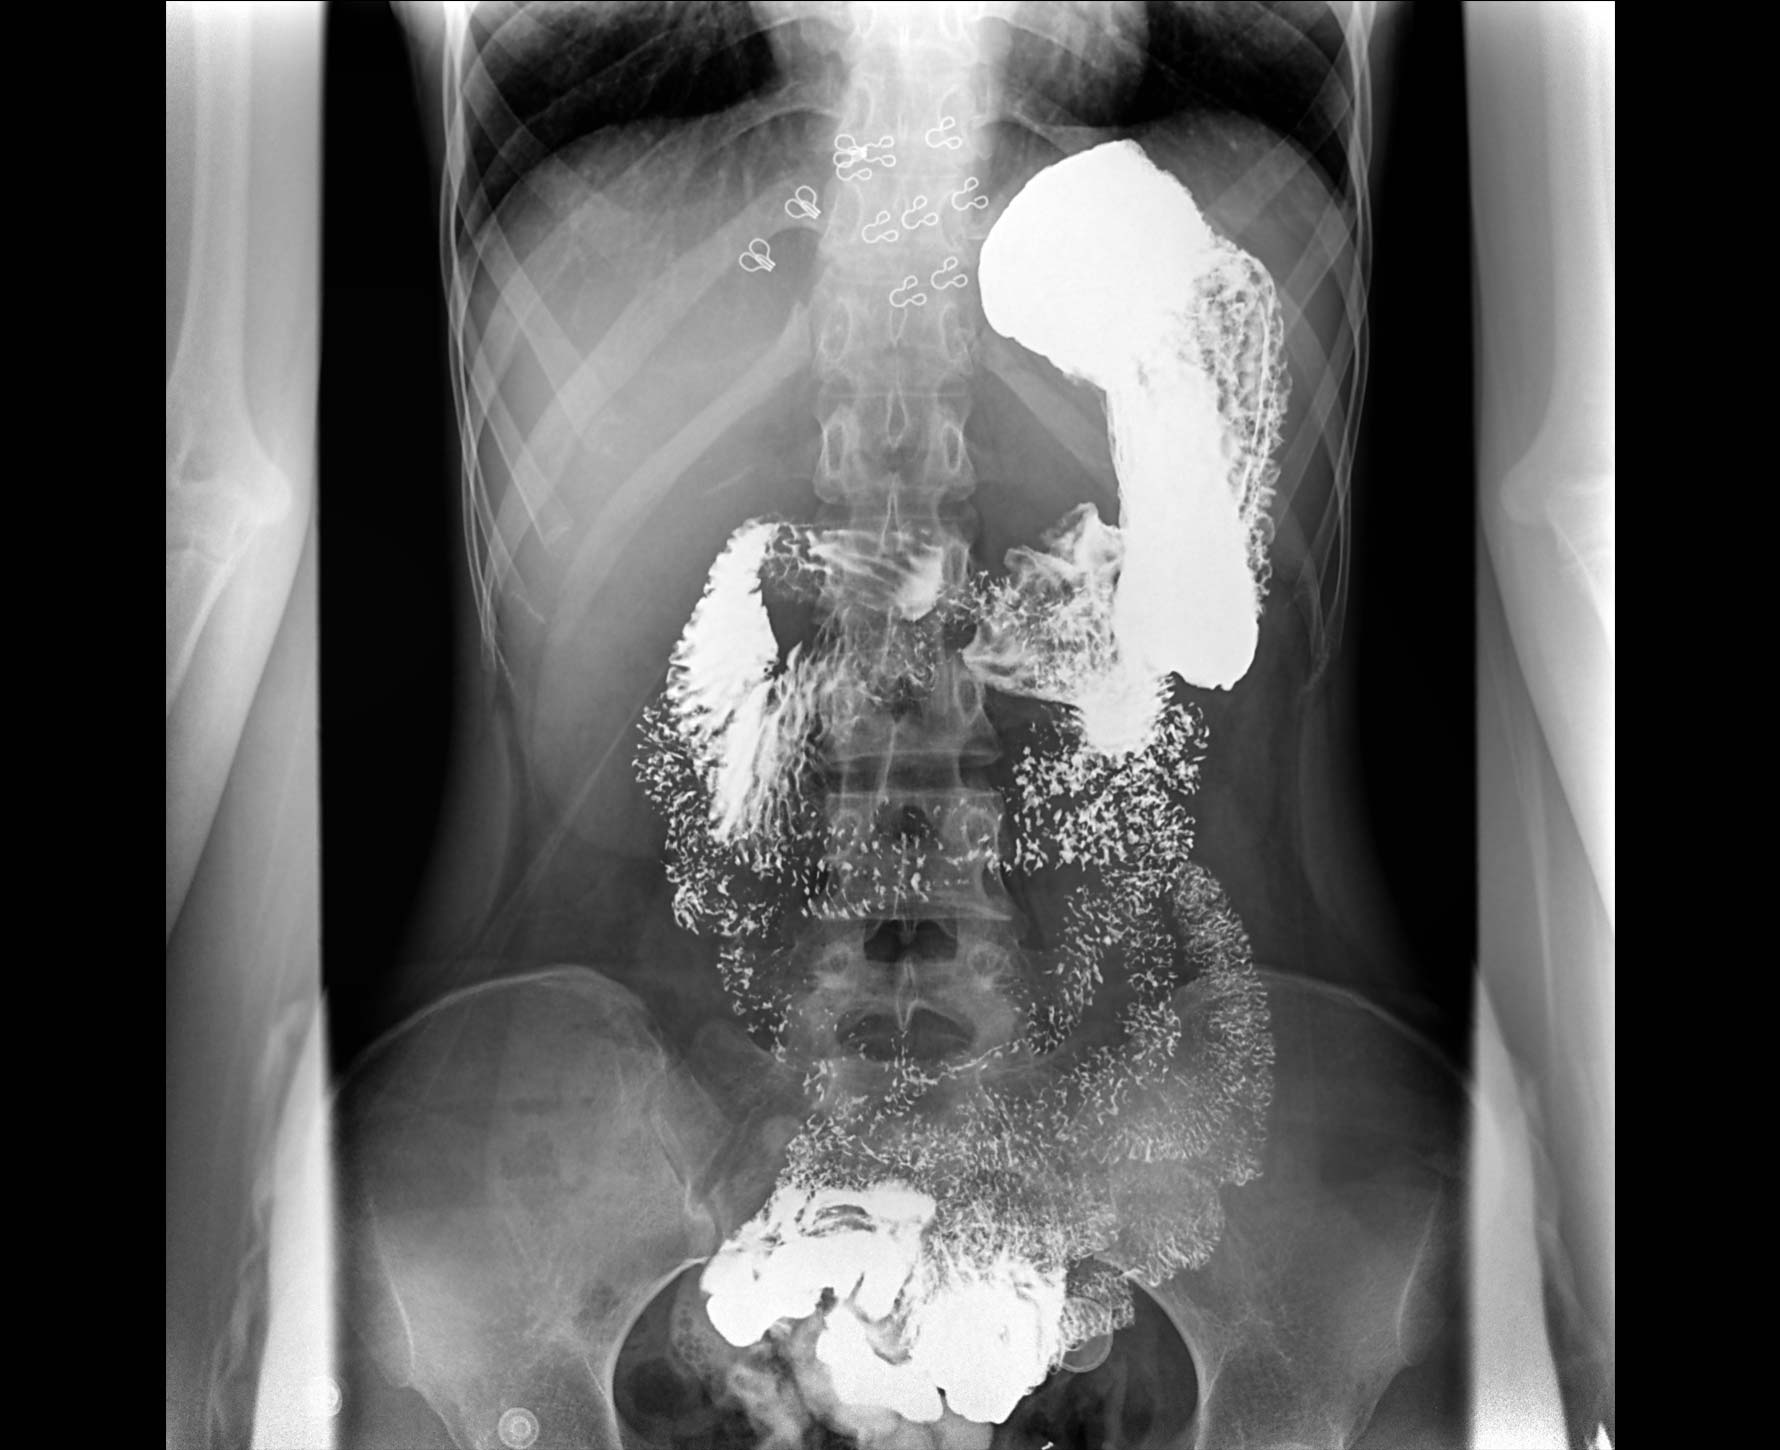

• 造影

适用于各种普通

及特殊胃肠造影检查

• 特有视频保存与回放功能

对胃肠造影检查影像实时保存,多次回放以便确定病灶部位,患者确诊好帮手,减少漏诊。